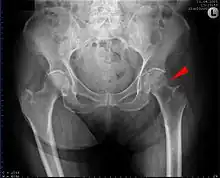

Intertrochanteric hip fracture in a 17-year-old male

Fracture (black arrow, pertrochanteric) versus a skin fold (white arrow).